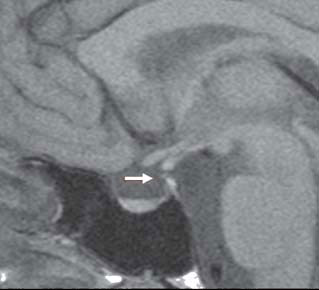

Magnetic resonance imaging (MRI) showed a partially empty sella, a very thin stalk and a small pituitary (Figure 1). The patient refused further dynamic hormonal tests to adequately study the adrenal-axis and the GH-axis and indeed did not even return to collect our discharge summary report with her final diagnosis or her prescriptions.

Figure 1. Sagittal T1-weighted magnetic resonance imaging showing a partially empty sella, a thin pituitary stalk (arrow) and a small pituitary. No alteration of the signal is given by the pituitary gland, indicating absence of focal abnormalities.